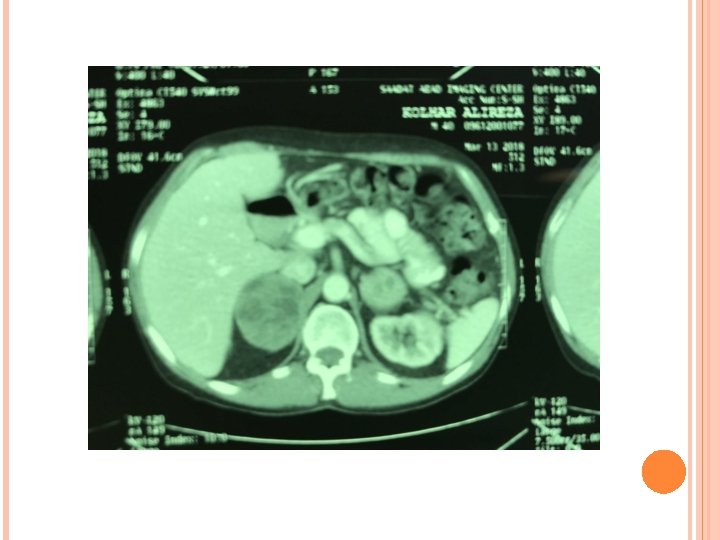

A CT of abdomen/pelvis revealed a round, heterogenous solid, 5/6 cm mass in right adrenal and 3/8 cm mass in left adrenal.